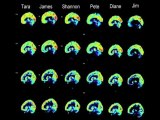

Vitamins for memory-Jim Fallon-Part2